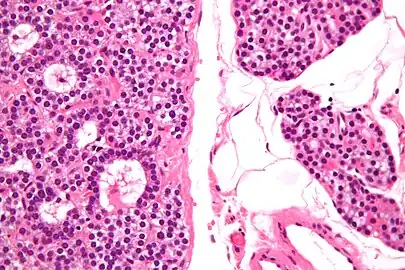

Normal parathyroid gland with prominent adipose tissue is seen on the right of the image.-High magnification -

Intermediate magnification -

Histopatholgical image of parathyroid adenoma in a patient with primary hyperparathyroidism. Hematoxylin and eosin stain. -

Histopatholgical image of parathyroid adenoma in a patient with primary hyperparathyroidism. Hematoxylin and eosin stain. Another view of the same lesion